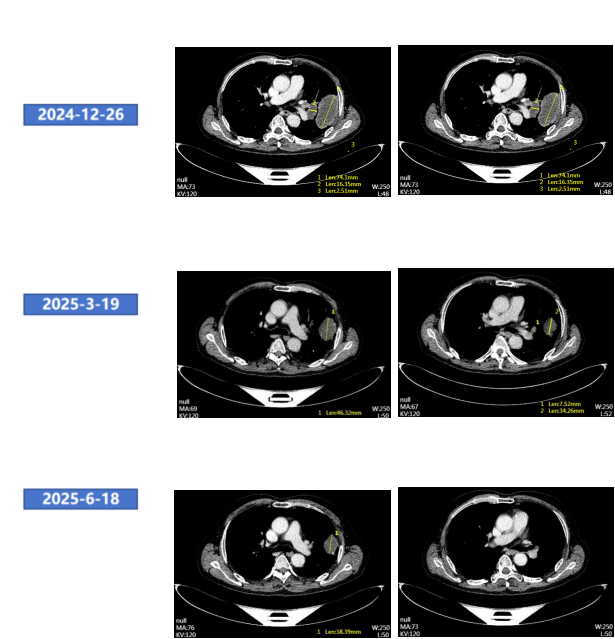

● 2024年12月26日颈胸腹盆CT增强:左肺上叶占位性病变(74mm),考虑癌,侵犯胸壁,伴左肺门淋巴结转移。

胸部腹部增强CT(2024年12月26日)

● 2025年3月19日颈胸腹部CT增强:左肺上叶病灶及左肺门淋巴结较前明显缩小。总体评效:PR(缩小38%)。

● 2025年6月19日颈胸腹增强CT增强:左肺上叶病灶及左肺门淋巴结较前缩小。总体评效:持续PR(缩小49%)。

胸部腹部增强CT